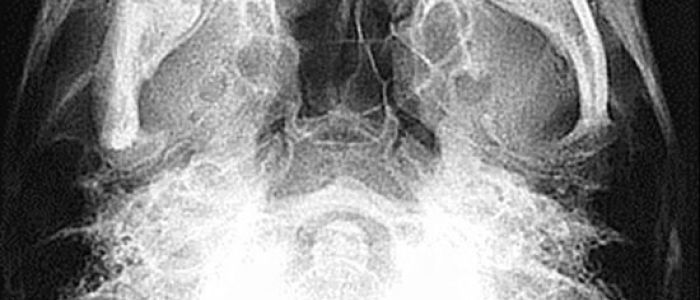

Radiografías Extraorales

Las radiografías extraorales se emplean cuando no es factible obtener información diagnóstica adecuada en las series de radiografías intraorales, es así que son utilizadas para observar un área grande de los maxilares y del cráneo en una sola radiografía. Los exámenes radiográficos extrabucales tienen el propósito de evaluar áreas grandes del cráneo, dientes impactados y patrones de erupción, crecimiento y desarrollo; examinar la extensión de lesiones grandes, traumatismos, articulación temporomandibular. Son de mucha utilidad principalmente en Ortodoncia y Cirugía Bucal.

Existen varias radiografías extraorales entre las cuales se tiene: